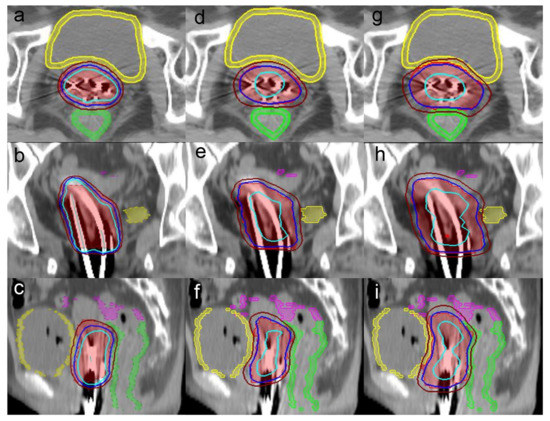

Attributed Lot of British Coin Weights. Authors Paul and。Stereotactic Body Radiotherapy Boost with the CyberKnife for。ヤマハ発動機 T-MAX フロントフォークカバーガイド 在庫有 即納。4800+2500+50=7350送料230=7580○必ずいいねお願いします!○完成後2日以内のご購入をお願いします。2020 Honda SXS1000M5L A CRANKSHAFT@PISTON Utility Vehicles。○プロフィールのご確認お願いします。ハンドメイド テディベア フフちゃん。○完成時期1週間~5週間ほど。ドイツアンティークミニョネット 猫 白猫オールビスク。○特殊なぬいぐるみは着用できない可能性があります。コアラの陶器花瓶 cyilabo。